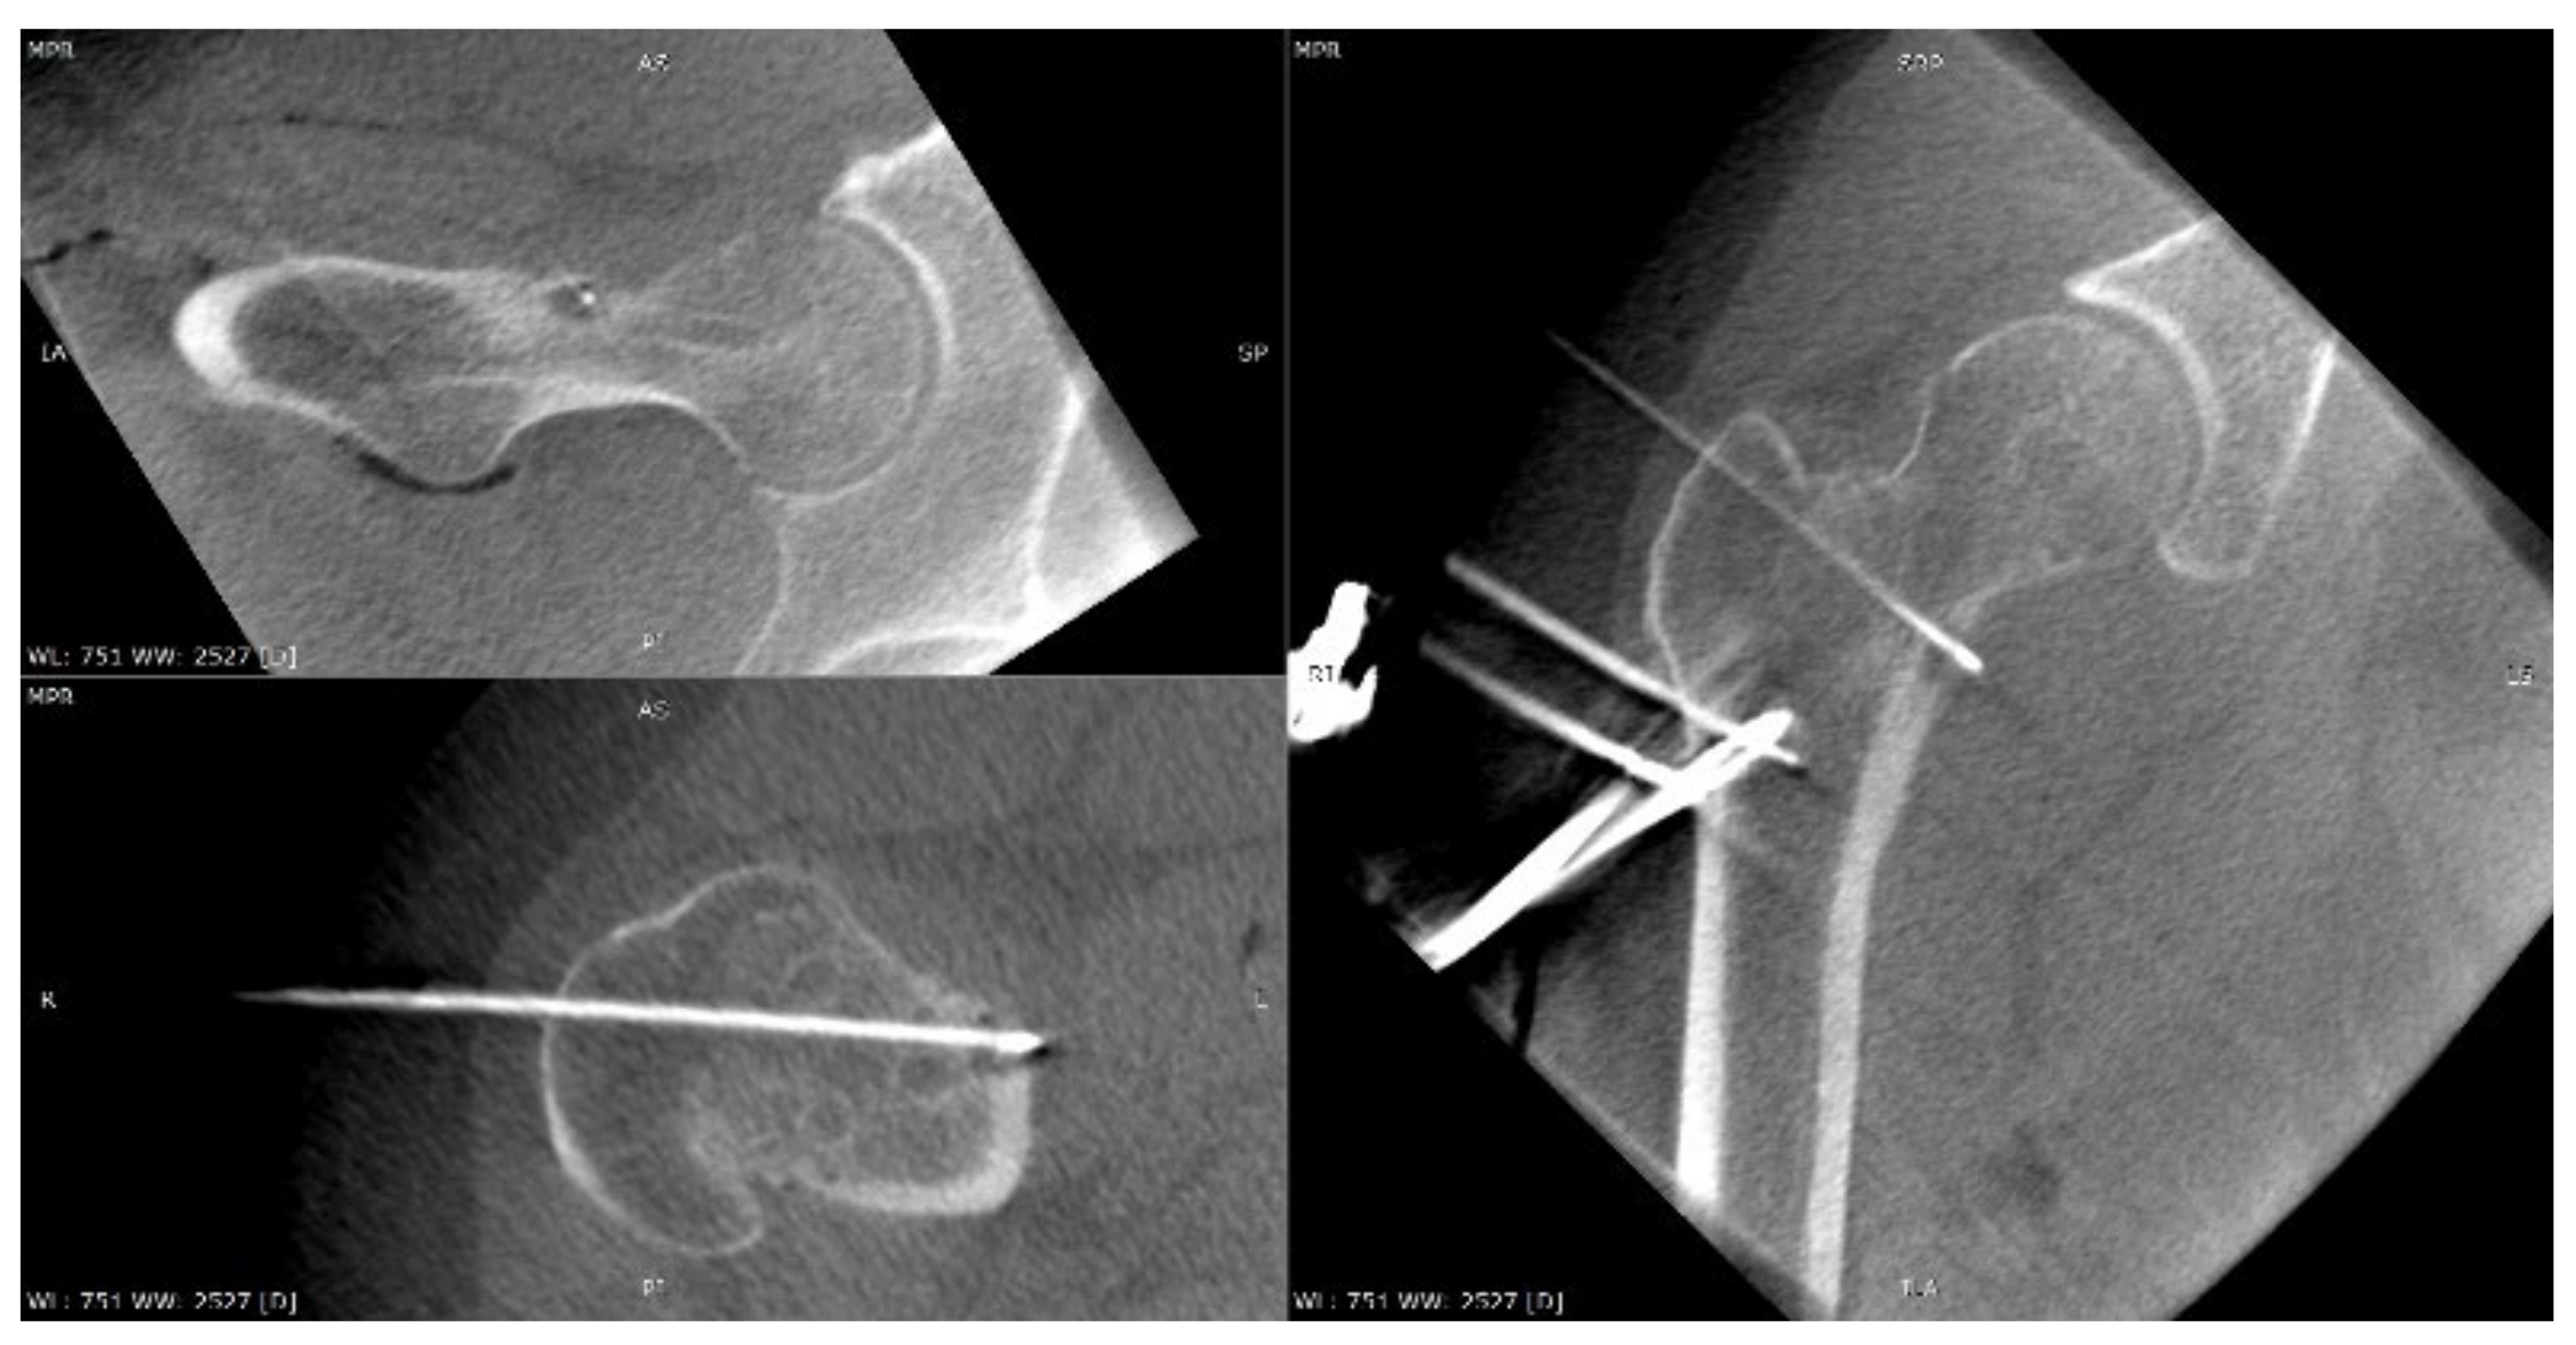

3.1. Case 1: OO Masking as Femoroacetabular Impingement (FAI)